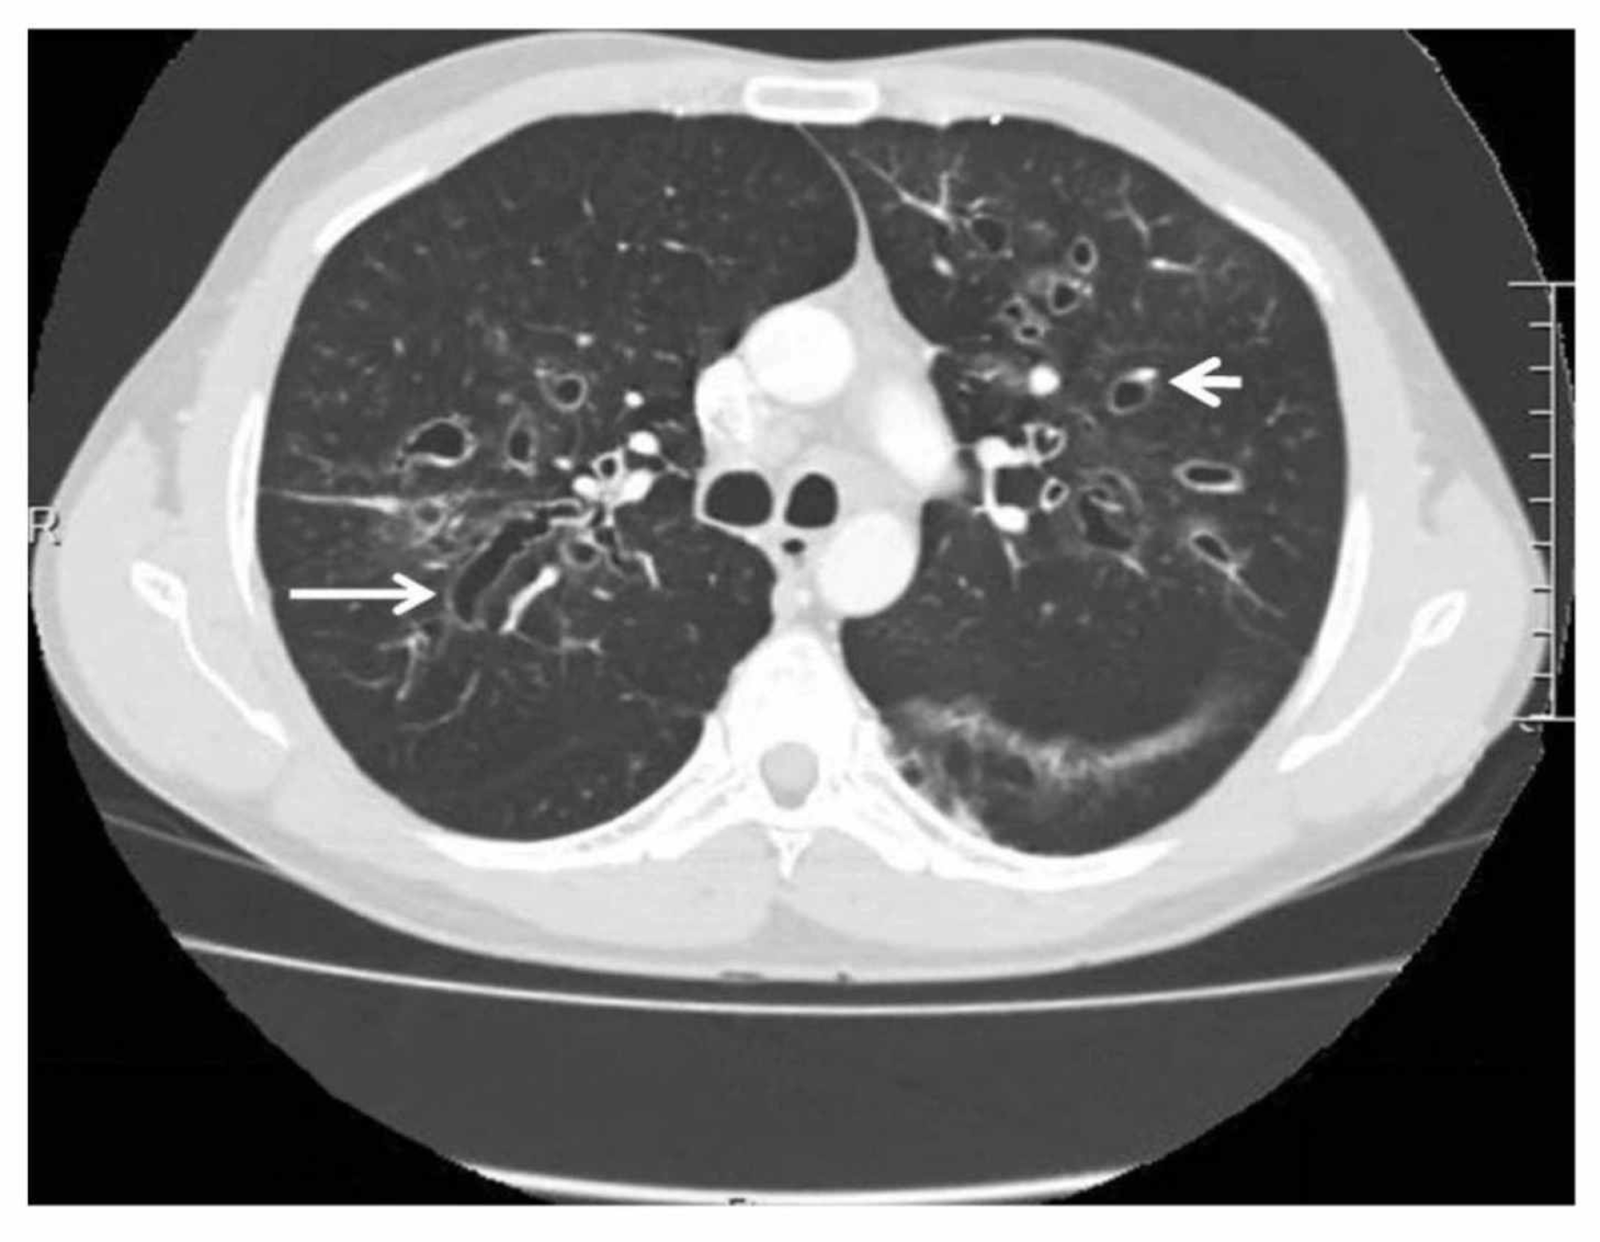

The ACS now recommends annual low-dose CT scans for people aged 50 to 80 who have a 20+ pack-year history of smoking, which was previously set at 30.

The ACS recommendation for lung cancer screening age has increased from 55 to 74 years old — to 50 to 80 years old. (iStock)

The screening age widened from the previous 55-to-74-year range — broadening eligibility to about five million more people.

Lung cancer can be treated successfully if it's detected at an early stage when the cancer is still small and hasn't spread, according to the ACS.